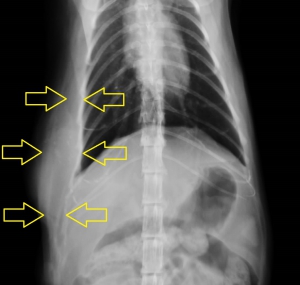

下写真は上記の部位の胸部レントゲン写真です。黄色矢印で挟まれた肉腫の占めるエリアが白く拡大しているのがお分かりかと思いますが、正常部位とはなだらかに連続しており境界がありません。また、左向き矢印で示されるように硬い腫瘤に胸壁が圧迫されて内側に変形しているのが分かります。